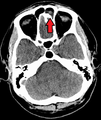

Left-sided maxillary sinusitis marked by an arrow. Note the lack of the air transparency indicating fluid in contrast to the other side.